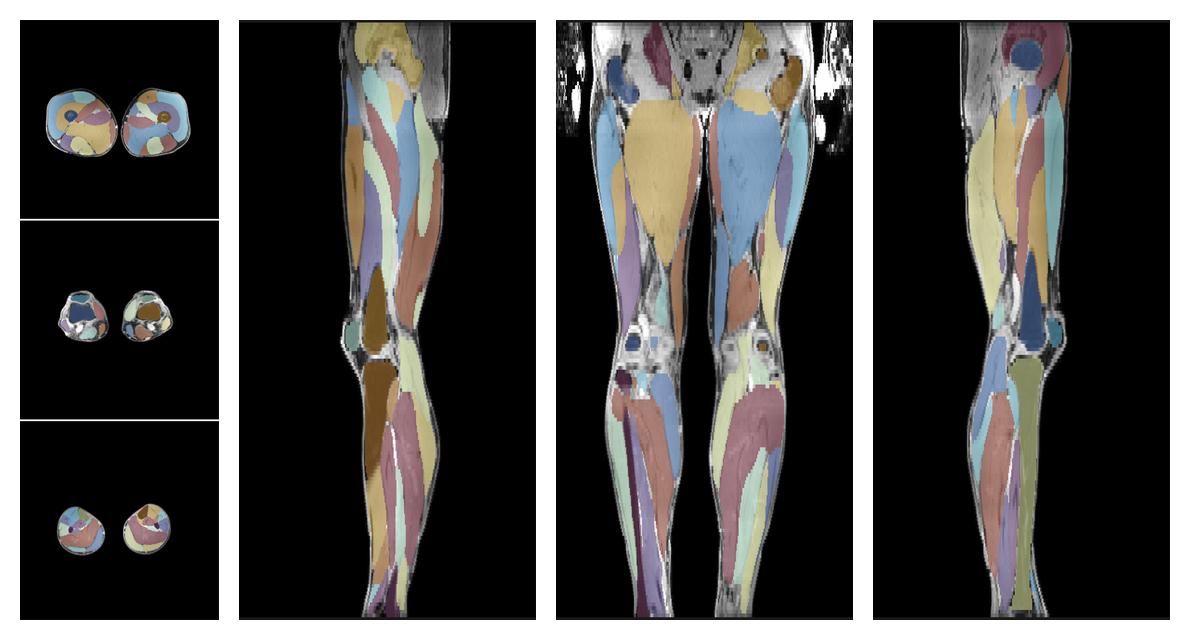

Muscle segmentation

Convolution neural network based (UNET) fiber automated muscle segmentation, for information look here».

• 3D volume render of automated muscle segmentation.

3D render of automated muscle segmentation labels generated using a CNN UNET.

• Automated muscle and bone segmentation.

Overlay of automated muscle segmentation labels on dixon water image.